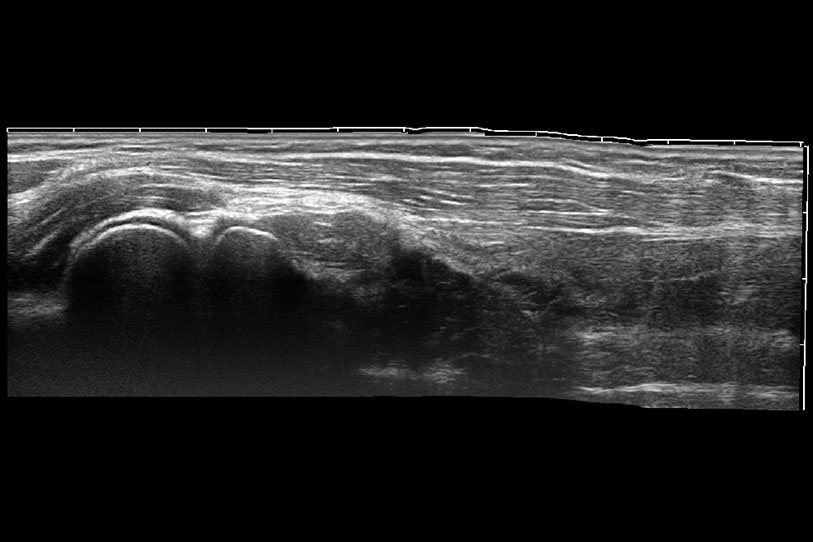

通過(guò)色彩血流和實(shí)時(shí)寬景相結(jié)合,可觀(guān)察到完整的靜脈或動(dòng)脈的血流,方便醫(yī)生檢查。實(shí)時(shí)掃查過(guò)程中,如有任何操作失誤也可以很容易地進(jìn)行回掃擦除,而不會(huì)中斷掃查。